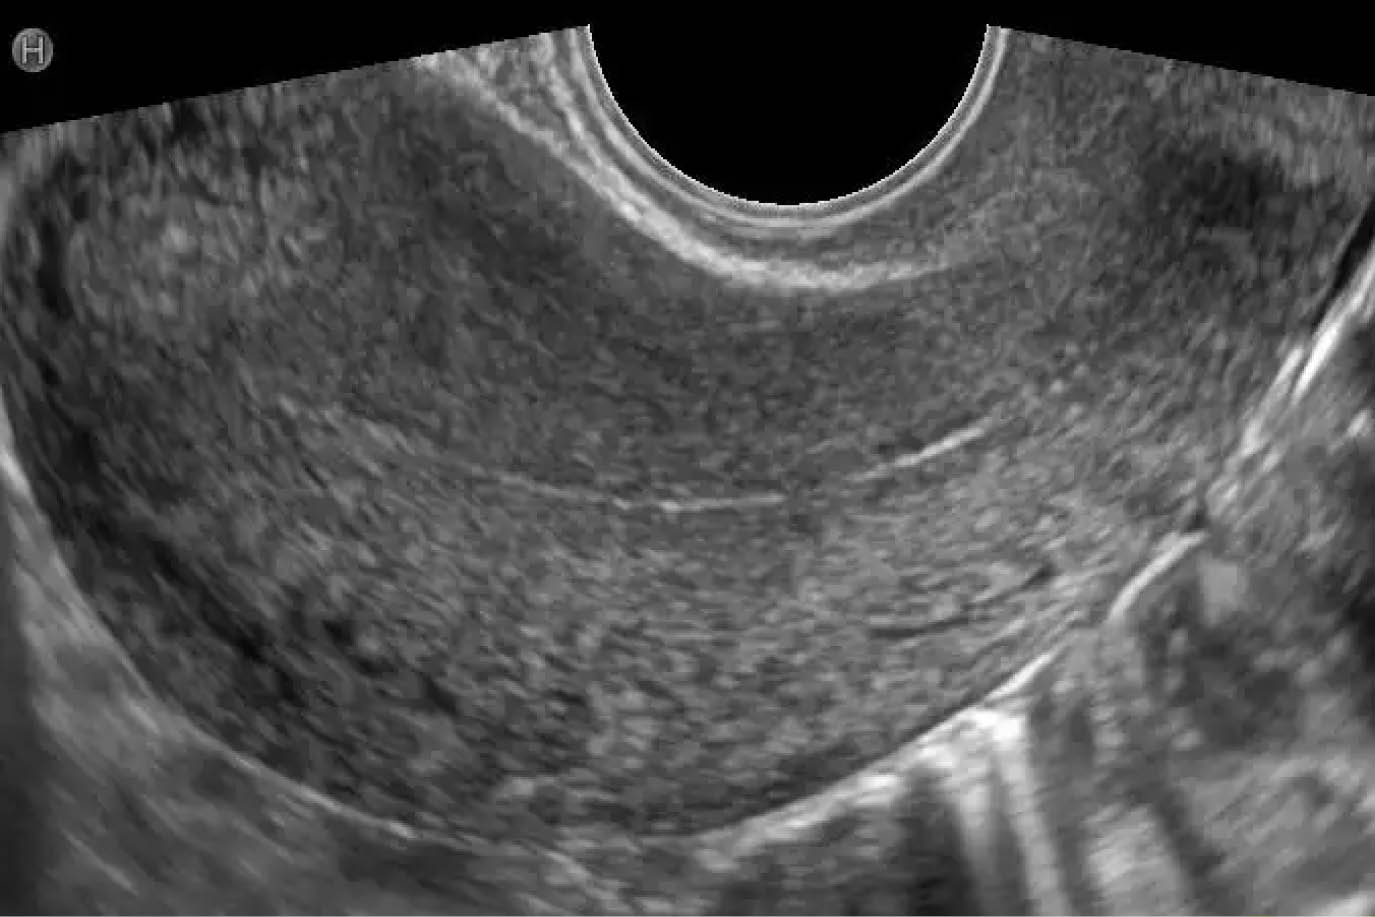

Медицинская диагностика: Гиперплазия эндометрия на УЗИ